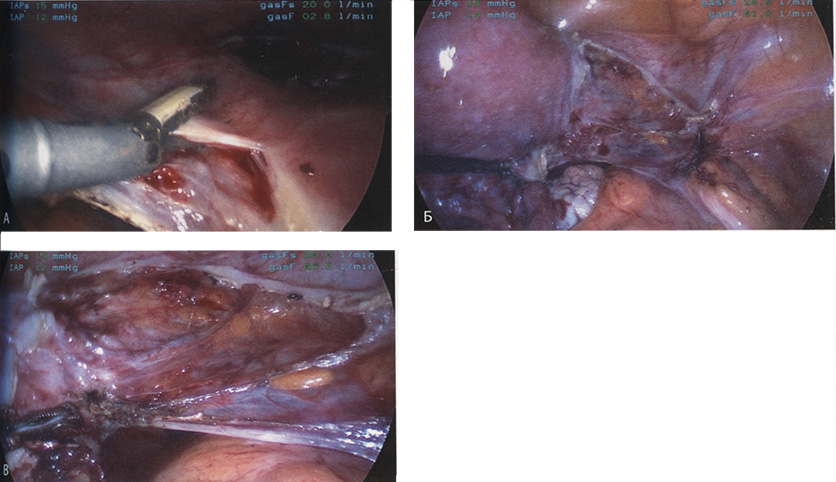

Если оставить в стороне эти достоинства и недостатки, то техника лапароскопической гистерэктомии фактически идентична технике лапаротомической гистерэктомии. В самом начале операции, если она выполняется лапароскопическим методом, необходимо осмотреть всё операционное поле, воспользовавшись для этого панорамным обзором (рис. 12-33—12-37). Операцию начинают с коагуляции и пересечения круглых связок, чем обеспечивается доступ к широкой связке (рис. 12-38—12-40). Брюшину, переходящую с купола мочевого пузыря на переднюю поверхность матки, вскрывают. Пузырь отсепаровывают от матки острым путём (рис. 12-41). После этого вскрывают задний листок широкой связки, а затем принимают решение, оставлять или удалять яичники. Если принято решение оставить яичники, то коагулируют и пересекают собственные связки яичников и маточные трубы (рис. 12-42). Если принято решение удалить яичники (то есть выполнить сальпингоофорэктомию), то с обеих сторон выполняют диссекцию мочеточников от воронко-тазовых связок, которые затем отсепаровывают, коагулируют и пересекают (рис. 12-43). Затем ткань широкой связки отделяют от маточных сосудов (отпрепаровывая их), изолировав, таким образом, мочеточники от маточных сосудов (рис. 12-44 А). Восходящие ветви маточных сосудов коагулируют справа и слева, а затем пересекают (рис. 12-44 Б, В).

Коагулируют и пересекают так называемые поддерживающие связки матки (рис. 12-44 Г, Д). Возможно, потребуется разделить ткани, соединяющие мочевой пузырь с передней стенкой влагалища. После этого вскрывают влагалище и коагулируют все кровоточащие сосуды. Если хирург владеет методами лапароскопического наложения швов, то он зашивает культю влагалища. Предварительно матку извлекают через влагалище или путём морцелляции (рис. 12-45 и 12-46).

Рис. 12-44. А. Маточные сосуды выделены на протяжении, коагулированы и пересечены. Б. Увеличенное изображение пересечённой кардинальной связки. В. Отсечена соединительная ткань, поддерживающая шейку ха. Г. Увеличенное изображение В. Д. Коагулирована и пересечена крестцово-маточная связка.